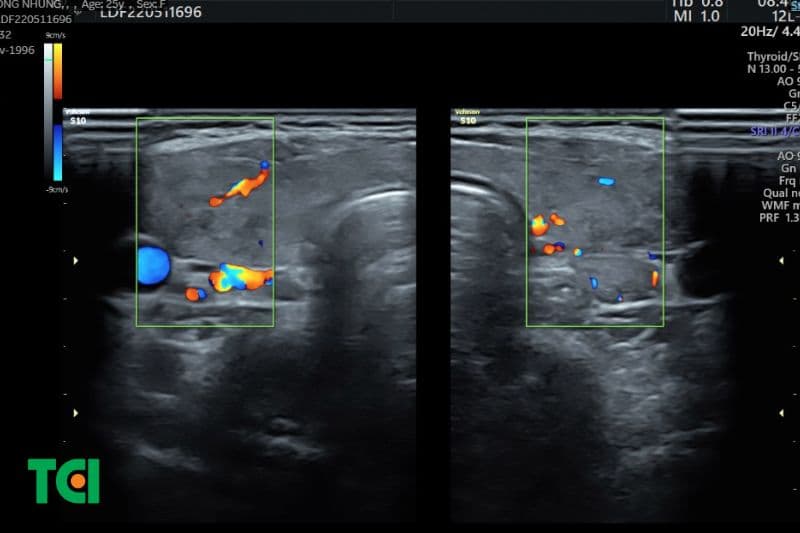

Không chỉ có giá trị với nhân giáp, siêu âm 4D còn hỗ trợ đánh giá các bệnh lý viêm tuyến giáp như viêm tuyến giáp Hashimoto hay viêm tuyến giáp bán cấp. Hình ảnh tái tạo đa chiều kết hợp Doppler màu giúp ghi nhận sự thay đổi về cấu trúc mô và mức độ tưới máu, từ đó phản ánh mức độ hoạt động viêm.

Nhờ khả năng hiển thị đồng thời hình thái học và huyết động học, phương pháp này cho phép đánh giá chính xác hơn đặc điểm nhân giáp, mô tuyến và hệ thống mạch máu nuôi dưỡng, từ đó nâng cao độ tin cậy trong chẩn đoán.

Nhân tuyến giáp là một trong những bất thường thường gặp nhất trên siêu âm. Với công nghệ 4D, bác sĩ có thể quan sát hình dạng không gian của nhân giáp, đánh giá bề mặt, cấu trúc bên trong cũng như mối liên quan với mô lành xung quanh. Điều này đặc biệt hữu ích trong việc nhận diện các dấu hiệu nghi ngờ ác tính như bờ không đều, vi vôi hóa hay tăng sinh mạch máu bất thường.